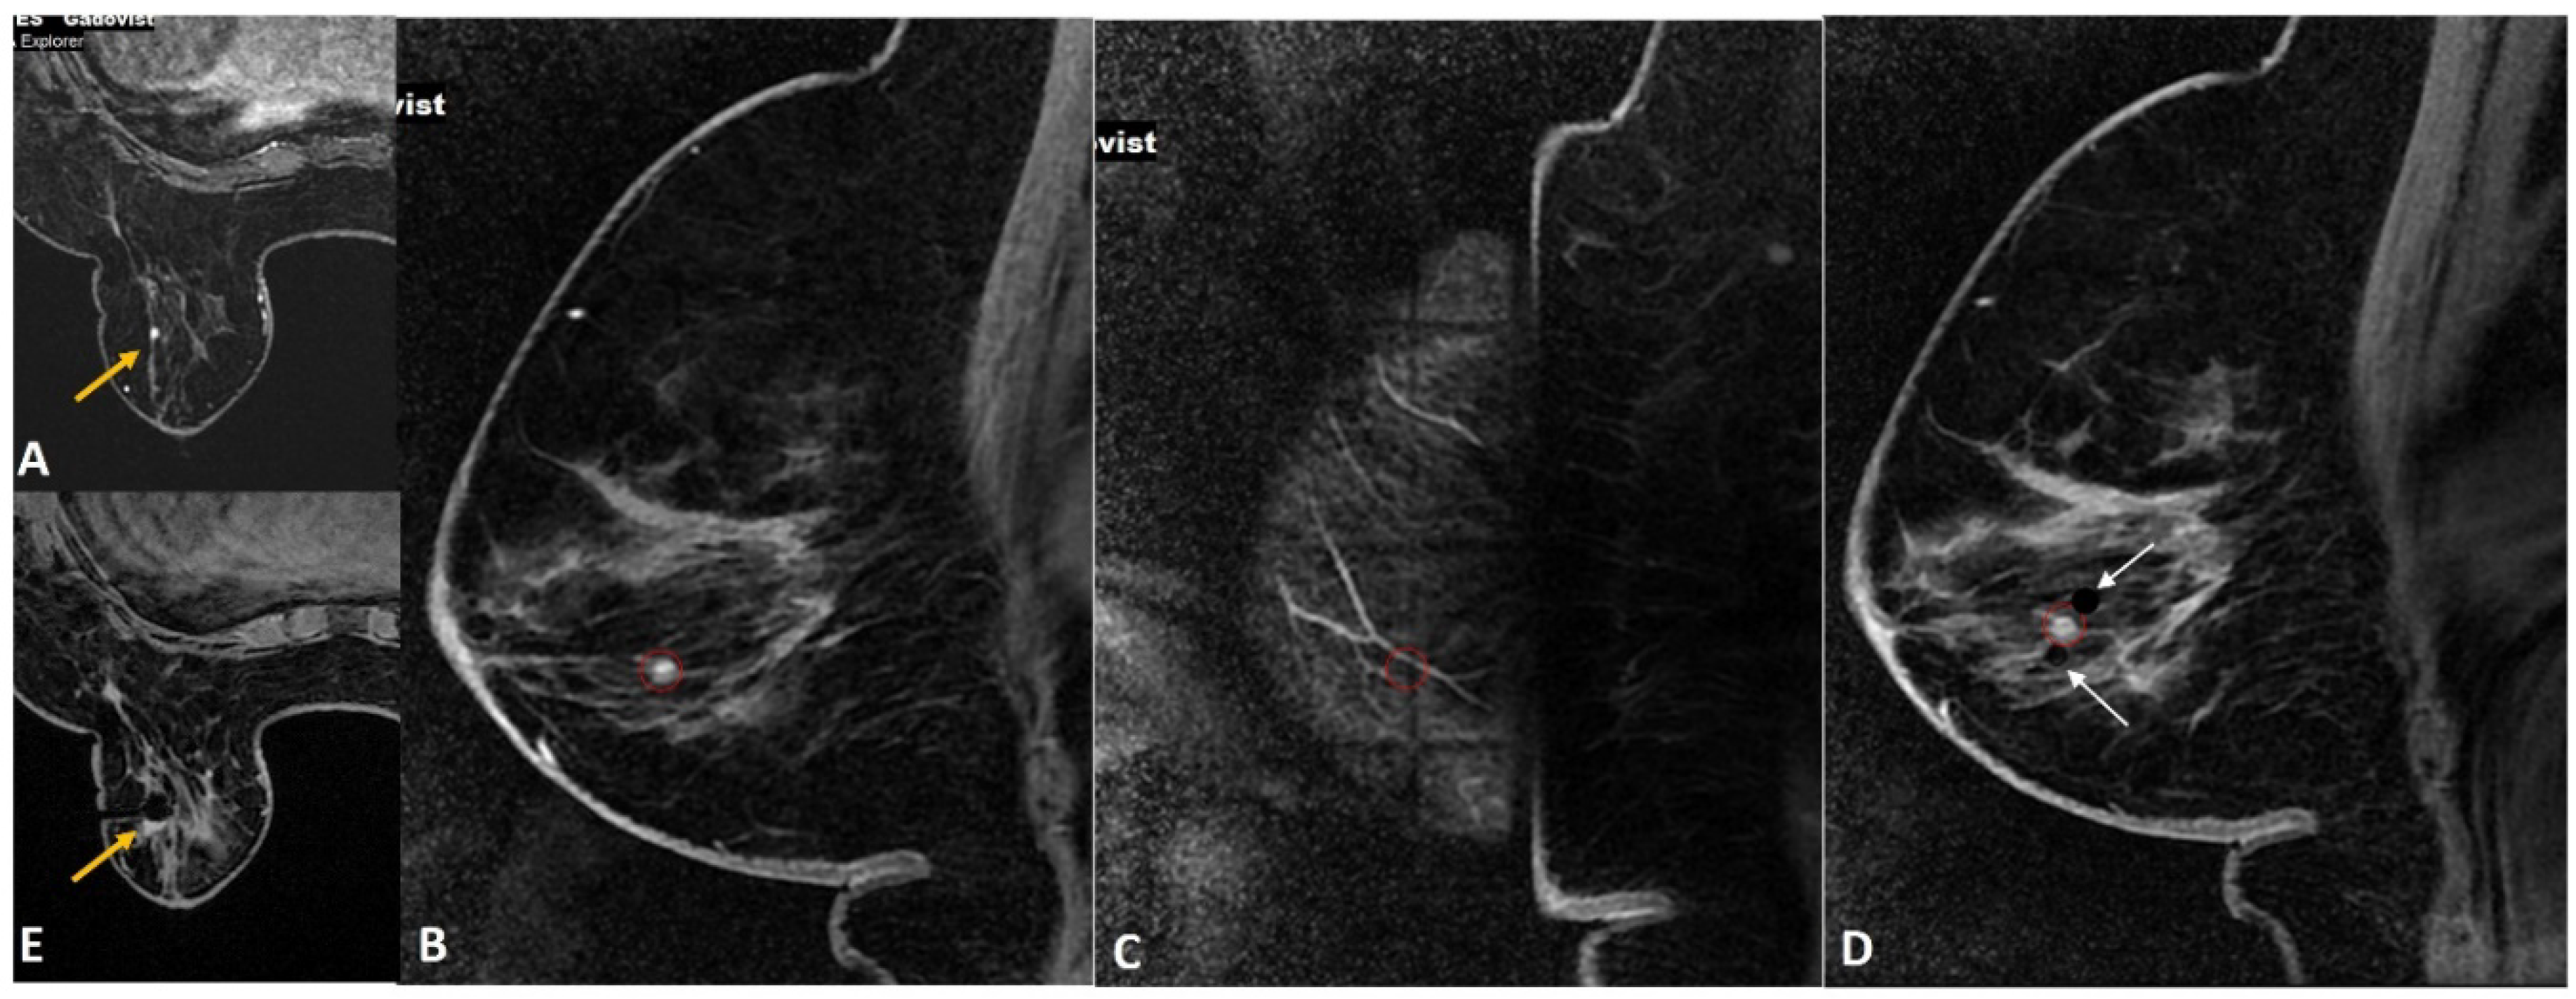

Figure 7.

(A). High-risk screening in a BRCA 2 woman showed a new 4-mm enhancing focus in the left breast (yellow arrow). (B). Sagittal image on the biopsy day showed the target focus enhancing well (red circle). (C). During targeting, the entry point was noted to fall on the “cross” of the grid (red circle), which blocked the ideal entry site. (D). In this case, we performed dual-needle targeting though diagonally adjacent holes. Two obturators in these holes (white arrows) are seen adjacent to the target (red circle). Selected directed sampling through both these needles towards the target would increase the chance of getting the tiny lesion biopsied adequately. (E). Post biopsy hematoma cavity (yellow arrow) was seen at the target site with non-visualization of the target suggesting adequate sampling. The histology was proven as 3-mm invasive tubular carcinoma.